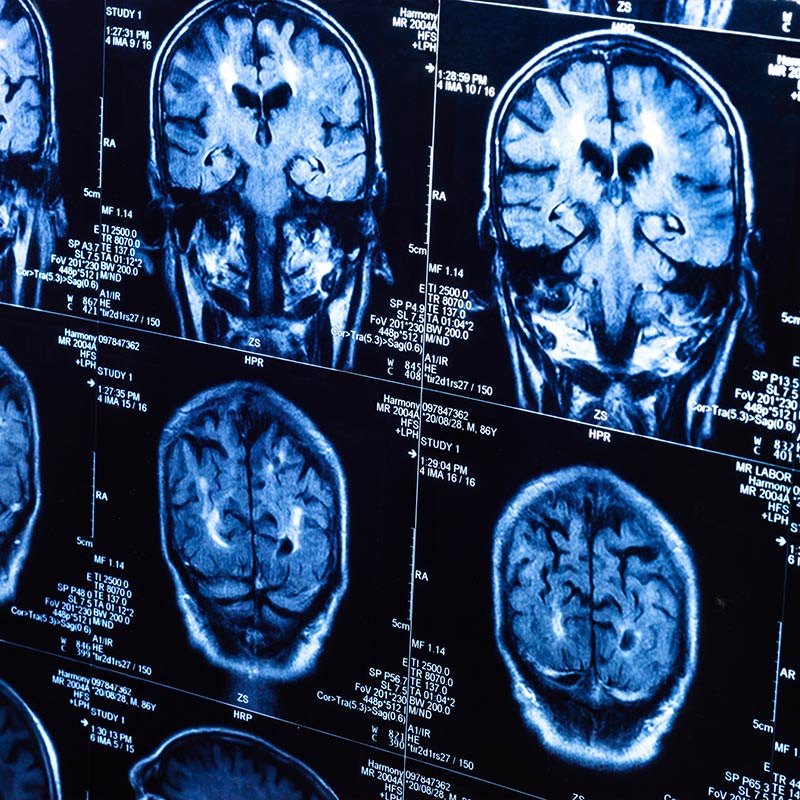

La Unidad Asistencial de Neurología del Centro Médico IMQ Amárica tiene como objetivo el estudio, diagnóstico y tratamiento de todas las enfermedades que afectan al Sistema Nervioso Central (cerebro y médula espinal), Periférico (nervios y músculos) y Autónomo (conjunto de nervios que regulan el funcionamiento de vísceras o de funciones automáticas como la respiración, etc).

Trata los trastornos del sistema nervioso. Se ocupa de la prevención, diagnóstico, tratamiento y rehabilitación de todas las enfermedades que involucran al sistema nervioso.